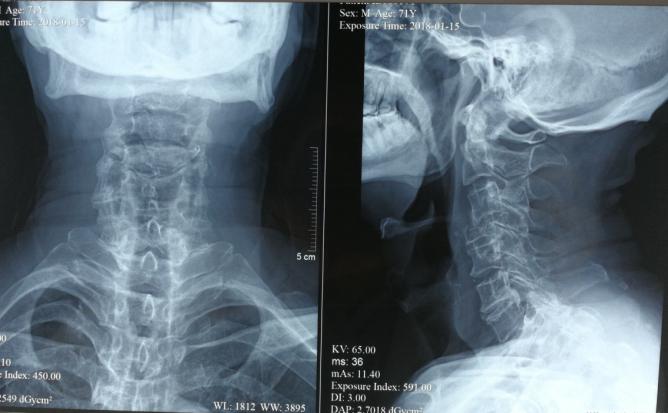

骨病骨肿瘤科近日完成 “颈4单椎体肿瘤伴病理性骨折行颈4全脊椎切除手术 ”1例。患者70岁男性,双肩部不适右上肢无力1月余,经检查提示颈4椎体单椎体肿瘤,颈椎椎体生理结构复查,涉及生命中枢脊髓和脑供血动脉椎动脉,该部位手术类似刀尖上跳舞,一不小心可导致患者的终身瘫痪或生命终结。 胡勇教授团队根据患者病情,制定精细手术方案,多套手术预案,采用颈椎前后联合入路实施颈4全脊椎切除+颈椎重建手术,术中既完整的切除了肿瘤,又精细地完成对脊髓和椎动脉的有效保护。术后5天患者即可在支具保护下起床活动并顺利康复出院,无伤口及神经并发症发生。胡勇教授指出:脊椎肿瘤的治疗需针对每个患者制定个性化治疗方案。颈椎邻近解剖结构复杂,肿瘤常常与椎动脉等血管、神经粘连,手术风险高、难度大,以往手术目的大多停留在提供组织学诊断、神经减压、减轻疼痛,而手术切除通常采用颈椎病或外伤的椎体次全切除或次全椎节切除的模式,显然难以达到肿瘤病灶彻底切除的目的。全脊椎切除+脊柱重建手术越来越多地被应用于脊柱原发恶性肿瘤和孤立性转移肿瘤,全脊椎切除能显著降低脊椎原发性骨肿瘤局部复发率,改善脊髓神经功能, 可以减少术中出血和肿瘤细胞残留,提高患者治愈率和生存率。